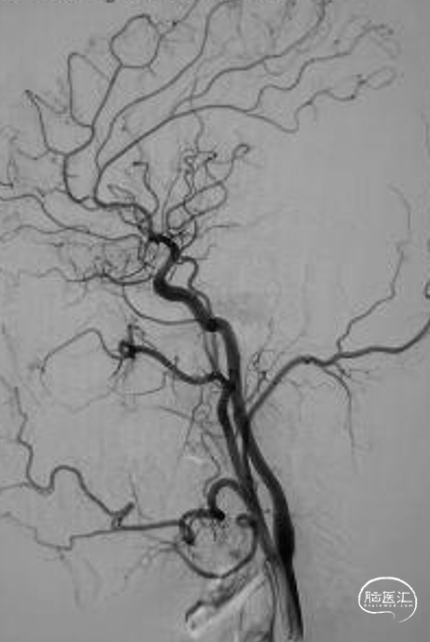

释放自膨式闭环支架 4*16mm后造影。

最后正侧位造影。

正位

侧位